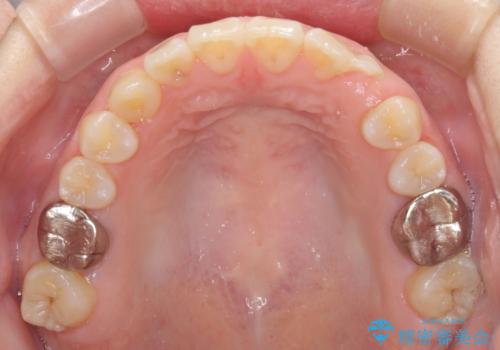

受け口で開咬を急速拡大装置とインビザラインで改善 欠損部分はインプラントにて補綴治療

- 前歯の開咬と、受け口による咬み合わせの悪さを気にして来院された患者様です。

左上は後続永久歯の欠損によりスペースがあり、矯正治療と並行してインプラントあるいはブリッジによる補綴治療が必要な状況でした。

上顎歯列が狭窄していたため、急速拡大装置により上顎骨を側方に拡大し、その後インビザラインにて矯正治療を行うこととしました。